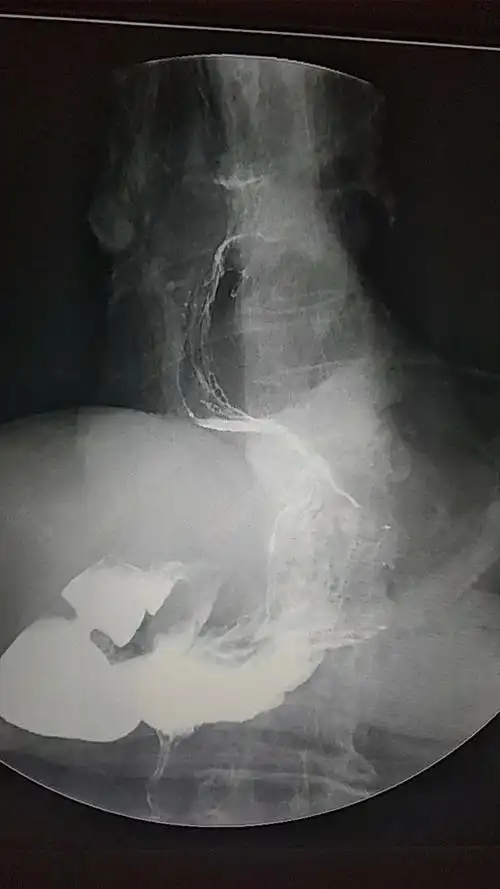

上饶市首例腹腔镜食管裂孔疝修补术

食管裂孔疝

食管裂孔疝的微创手术治疗